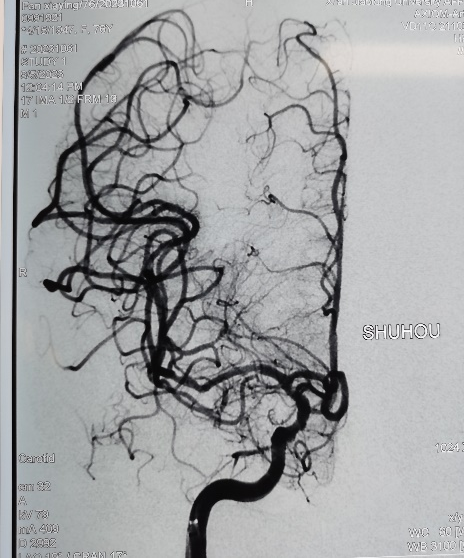

右侧大脑中动脉闭塞再通术后